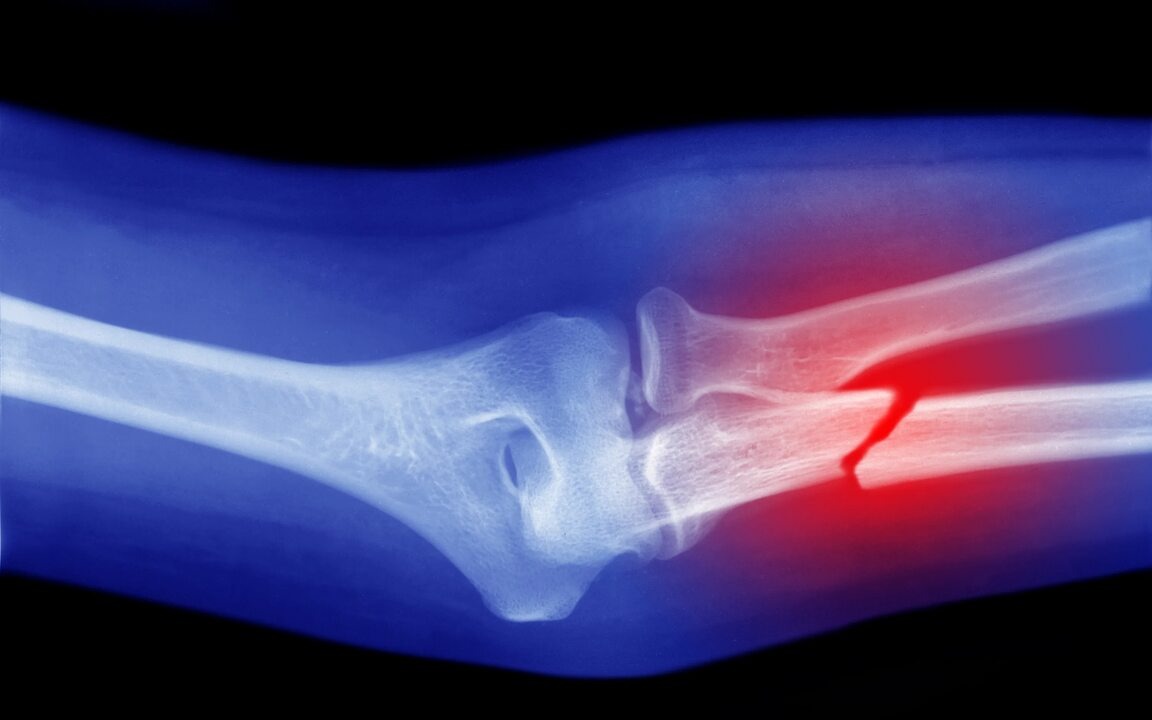

Знаете, что самое страшное в высоком паратгормоне (ПТГ) на гемодиализе? Он не просто вредит костям — он делает их хрупкими, как стекло. Можно сломать руку или ногу, просто неудачно повернувшись во сне. Я прошел через это дважды.

- Кости становятся слабыми, повышается риск переломов.